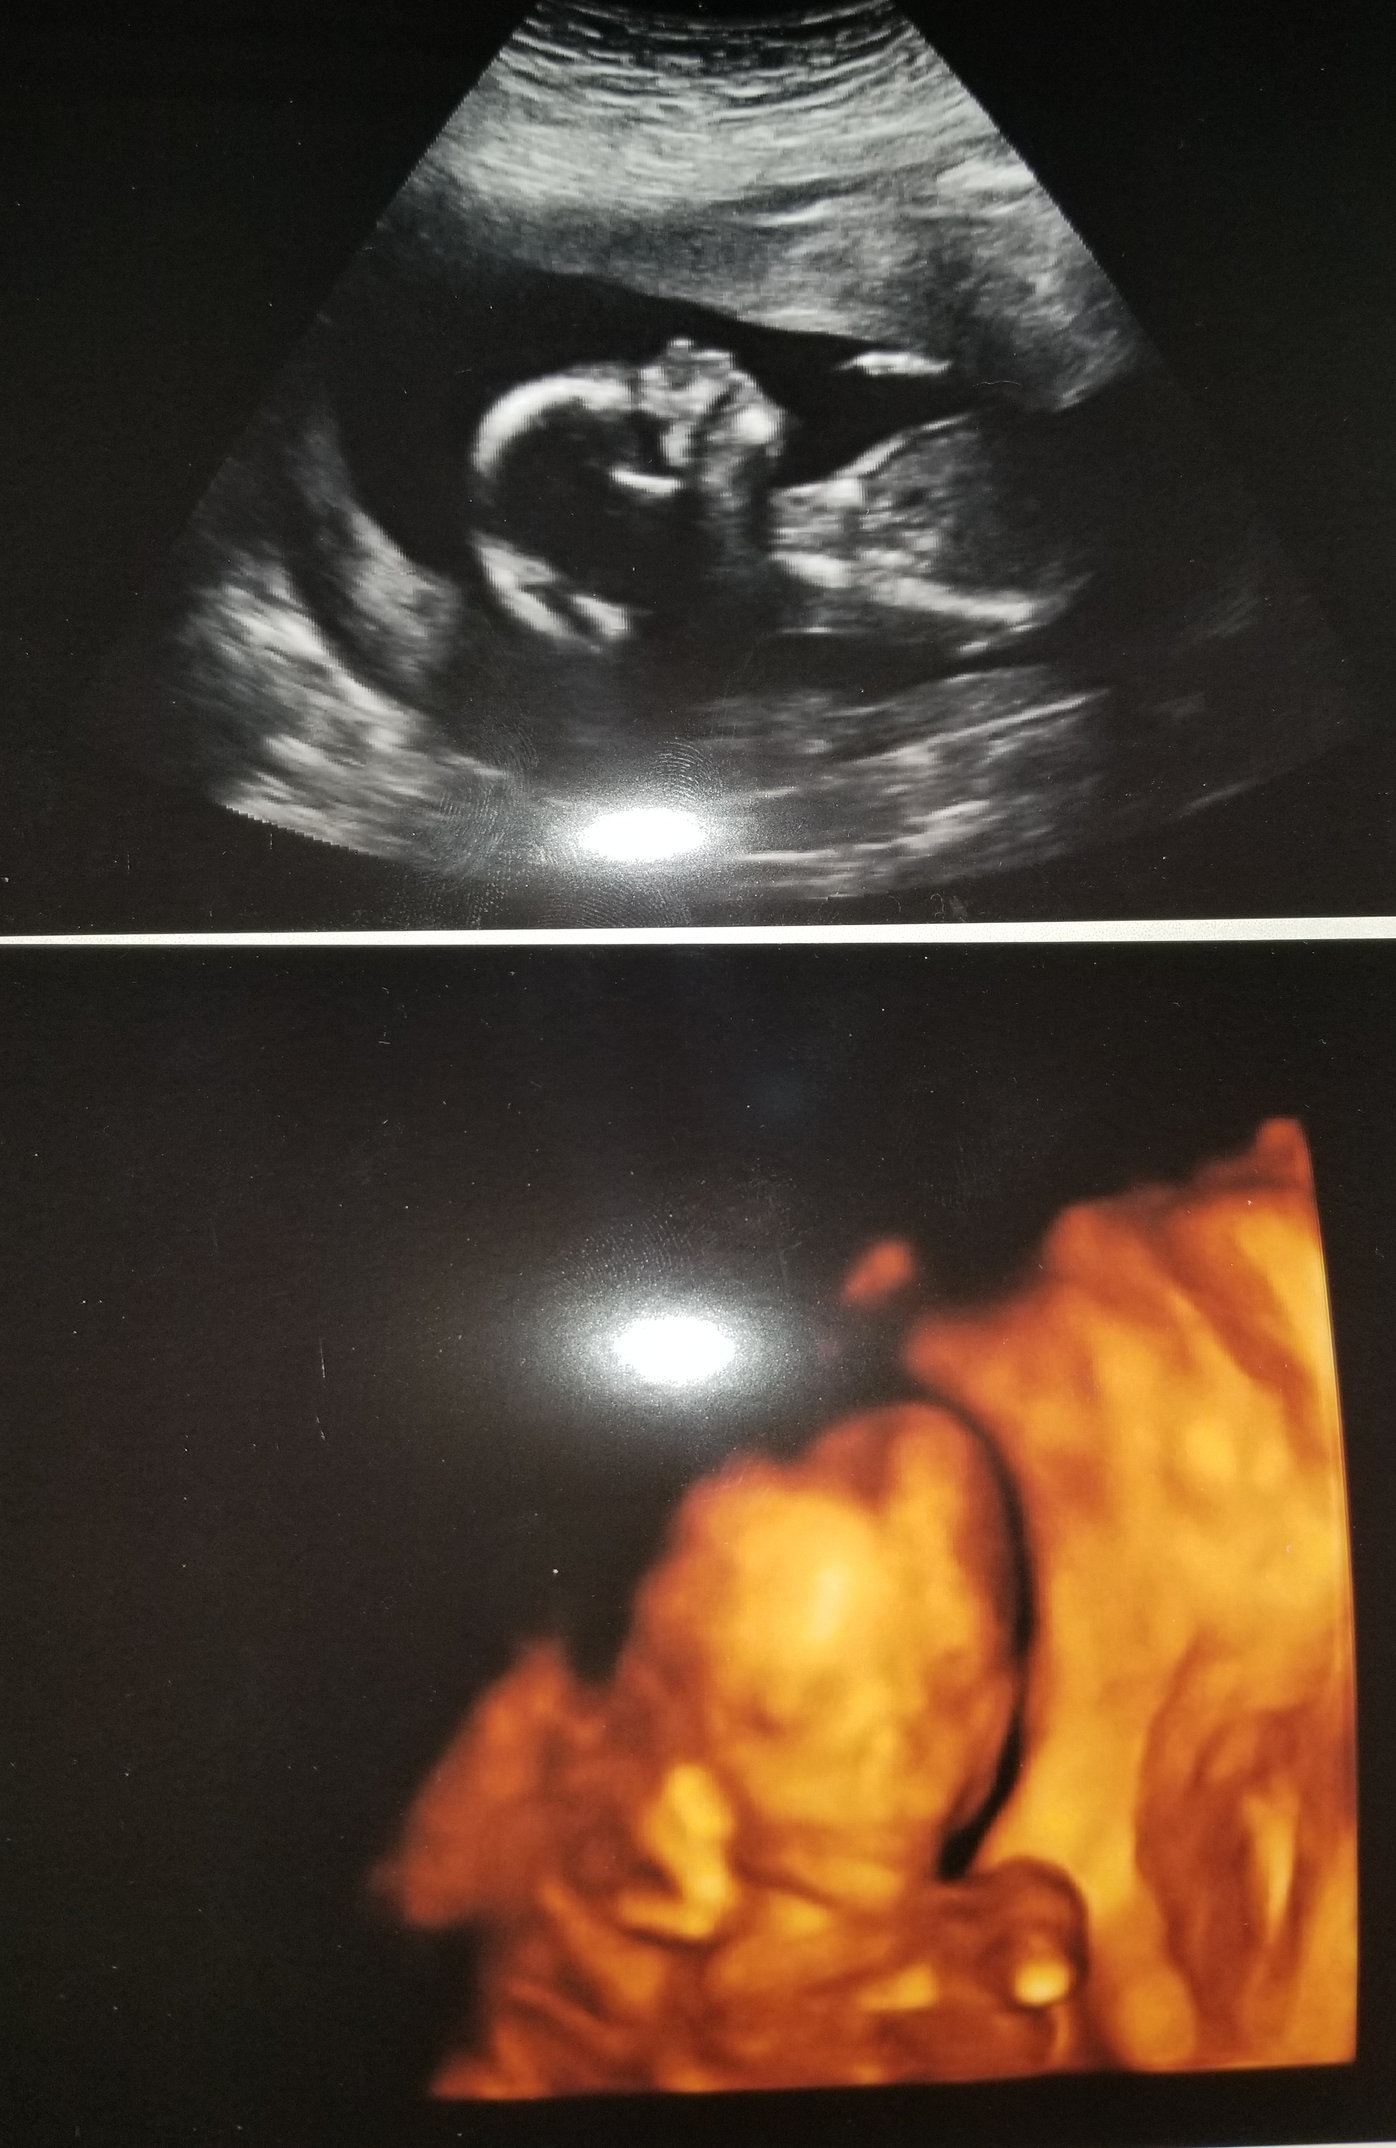

Baby G2 is still cooking. Anatomy scan today and everything turned out great. DS came with us and near the end when the tech turned it to 3D mode, he kept calling the baby a monkey and making monkey noises... 🐒

this baby looks a lot like DS did too. Which leads me to think this one is a boy. I’d love to be a boy mom but we’ll have to wait a bit longer to find out!